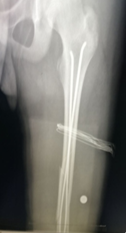

股骨干骨折弹性髓内钉固定术前

手术切口(仅为一个小孔)

股骨干骨折弹性髓内钉固定术后